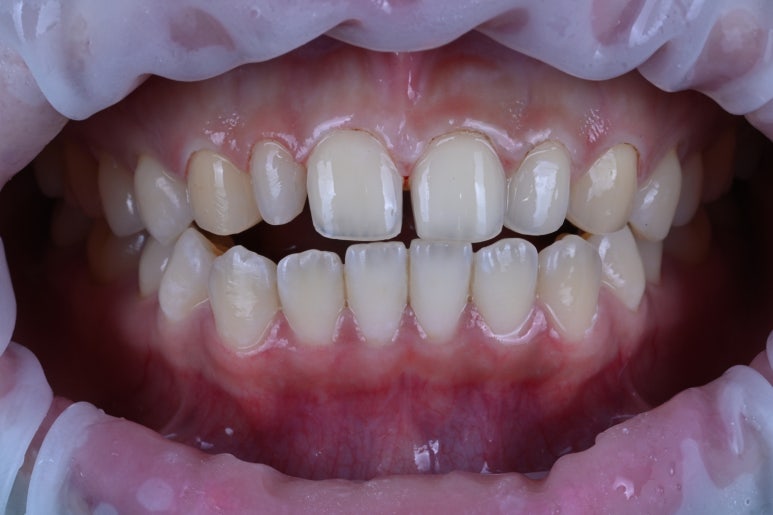

이번 환자분 같은 경우 밝은 색상의 치아도 함께 원하셨기에, 총 6개의 라미네이트 치료를 하기로 정해보았어요.

밝은 색상이면서, 반짝반짝 빛나는 라미네이트

결과적으로 섬세한 가공이 더 들어가는 저희 레브치과의 라미네이트가 결과 사진이 훨씬 예쁘답니다. :)